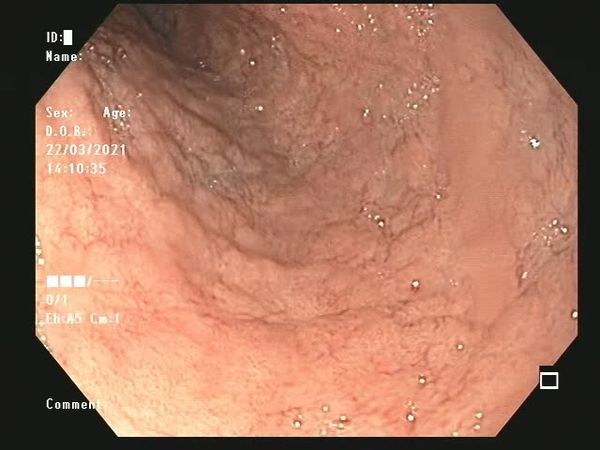

Doença Celíaca